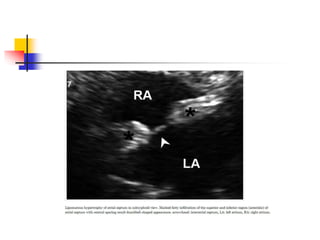

Lipomatous Hypertrophy of

the Atrial Septum

 lipomatous hypertrophy refers the condition of

prominent thickening of interatrial septum, usually > 2

cm, caused by excessive fatty infiltration.

 it actually represents the fat-filled extracardiac

spaces which is not encapsulated unlike true lipoma.

 Echocardiographic diagnosis is made when a marked

atrial septal thickening > 15-20 mm in the absence of

any other explanation for the abnormal thickening.

 region of fossa ovalis is typically spared, which

makes a characteristic dumbbell- or hour glass-

shaped lesion.

 Subcostal window can be best used . ME bicaval

view differentiates lipomatous hypertrophy from other

structures.

 superior and inferior "mass" is corresponds to the fat-

filled groove between atria (Waterston's groove) and

ventricles (inferior pyramidal space), respectively.